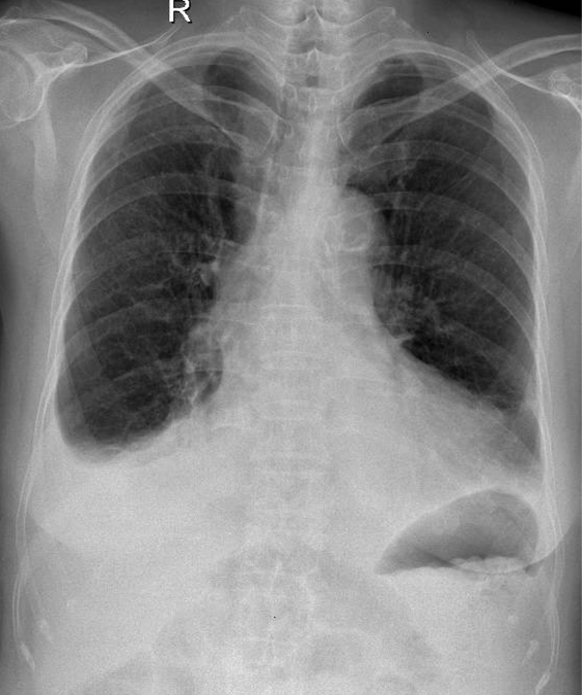

Hãy phân tích tình huống NỮ 89 tuổi

1-Tràn dịch màng phổi (P) lượng ít 2-Cung động mạch chủ đóng vôi 3-Tim (T) lớn